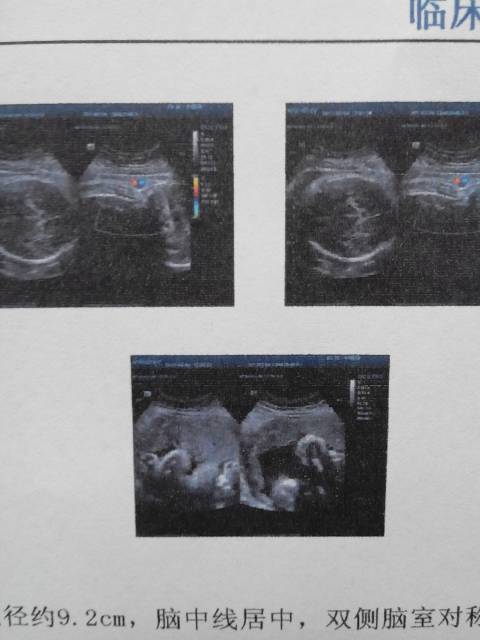

怀孕40周,刚做彩超,胎儿双顶径约9.2cm,脑中线居中,双侧脑室对称!等大!胎儿脊柱排列整齐,胸腹壁连线完整。可见胎动!胎心率约135/一次!请问谁能看出来,是男孩还是女孩啊

你好,根据报告单不能判断是男是女,只能通过B超动态观察胎儿性别。现在怀孕40周已到预产期很快就可以见到宝宝。

你好,这是正常成熟胎儿的超声报告,数据都是正常的,宝宝发育很好。这个上面看不出来性别,国内目前是禁止胎儿性别鉴定的,所以检查单上也不会有这方面信息体现。反正都快要生了,建议不必刻意追求,是男是女顺其自然,只要宝宝健康就好。